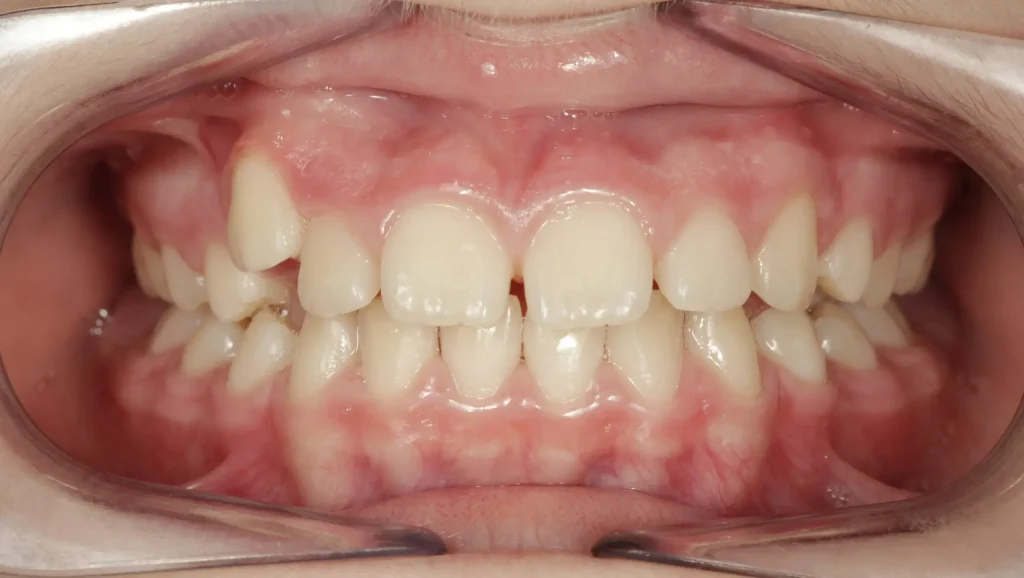

Al finalizar el tratamiento, se observan mejoras notables en la alineación dental. La mordida cruzada anterior ha sido completamente corregida, permitiendo que los incisivos superiores e inferiores se contacten adecuadamente cuando la paciente cierra la boca. Esta corrección restauró una oclusión equilibrada, mejorando la función masticatoria.

El apiñamiento de los dientes superiores ha sido completamente corregido, lo que permitió una alineación perfecta de los incisivos y una sonrisa más armónica. Los dientes ahora tienen un contacto adecuado y estéticamente agradable, proporcionando a la paciente una mayor confianza en su apariencia.

La salud bucal también ha mejorado, ya que el tratamiento ortodóntico ha optimizado la alineación dental, lo que facilita la higiene oral y reduce el riesgo de caries y enfermedades periodontales al evitar zonas de difícil acceso para el cepillo.